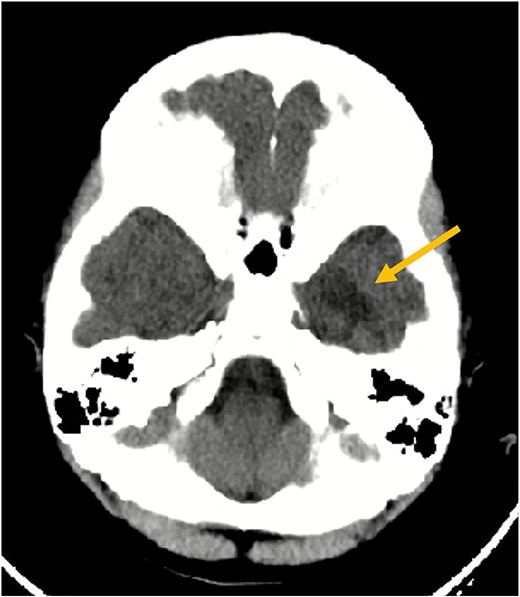

A 7-year-old girl with no significant past medical history presented after two minor head trauma events on the same day affecting her left temporal region. The first was a slip causing a direct impact, followed by a push from her sibling, after which she developed vomiting episodes. Physical and neurological examinations were normal. A non-contrast computed tomography (CT) scan excluded acute hemorrhage but revealed an ill-defined hypodense area in the left inferior temporal lobe.

MRI with and without gadolinium contrast identified a vascular lesion consistent with a DVA in the left anterior temporal lobe. This showed typical caput medusae venous morphology. Adjacent white matter T2/FLAIR hyperintensities were present without diffusion restriction or blooming on gradient-echo sequences. No abnormal contrast enhancement was noted, and major venous sinuses were patent (Figs 1 and 2).

Axial non-contrast CT scan of the brain. This image demonstrates an ill-defined hypodensity (arrow) in the left inferior temporal lobe (seen as a darker area). No acute intracranial hemorrhage or fracture was identified at the time of this initial scan.